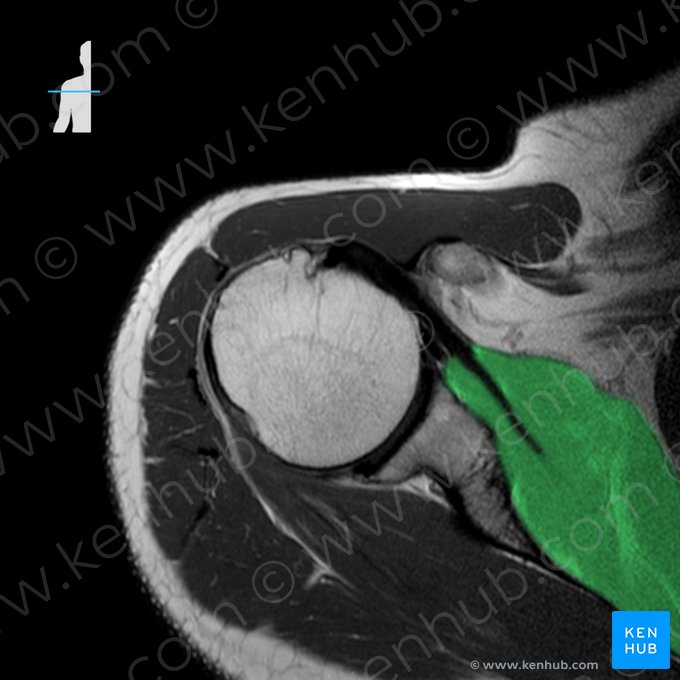

Ombro (RM)

A avaliação da articulação do ombro e dos tecidos moles adjacentes é melhor realizada com a ressonância magnética (RM). A modalidade em densidade protônica (DP) continua sendo uma das mais importantes sequências para a avaliação do sistema musculoesquelético.

Nas imagens ponderadas em DP, os ossos apresentam uma cor cinza clara ou quase branca, enquanto os ligamentos e cavidades aparecem em cor preta. Vamos analisar a RM de um ombro normal em vários níveis: